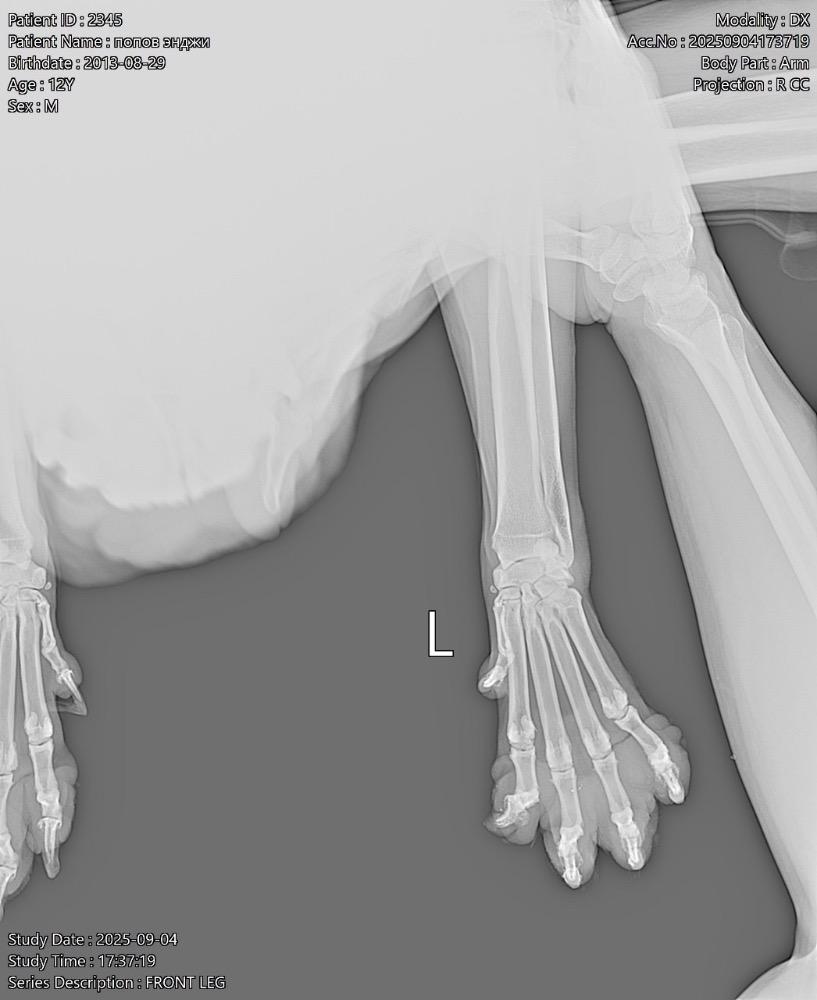

Татьяна13 Опубликовано 24 ноября, 2025 Опубликовано 24 ноября, 2025 (изменено) Всем здравствуйте! В июне началась проблема с лапами. Поставили диагноз-остеоартрит! Робексера+пк мерц прекрасно справлялись! На прошлой неделе собаке резко стало худо. Она начала часами без остановки дышать, иногда пристанывая. Было ясно, собаку что-то беспокоит…. В ветеринарке сдали анализ крови, сделали узи брюшной полости-ничего критичного… Врач решил, что Робексера уже не помогает, заменили на Фироко 227 мг + также оставили пк мерц. Добавили усросан, чтоб чуть полечить печень, так как небольшие отклонения есть… За 3 дня улучшений не вижу. Собака все также дышит без остановки часами, иногда пристанывая, второй день отказывается от корма (но вкусняшки ест), воду из миски пить отказывается (но пьет в ванной из душа и ест снег). Сегодня как будто начали отказывать задние лапы-она волочит ими. Вновь погнали в ветеринарку, они настаивают, что Фироко препарат хороший, сильнее его уже нет. Ждите! Чего ждать? Обезболивающее должно действовать же сразу…. Сказали, что тут скорее всего произошло защемление позвонка! Поэтому задние лапы не слушаются! И либо опять же ждите, либо делайте мрт, а потом операцию (собаке без пяти минут 12 лет, кстати!). Вдобавок выписали: Габапентин. В четверг хотят еще прокапать Хиовет. Сейчас, солнце мое спит, ходить не может. Когда просыпается, пытается встать и начинает дико плакать! И снова ложится! Люди, чем помочь собаке моей? Столько таблеток выписали… Как не навредить😭 У меня уже сердце болит… Изменено 24 ноября, 2025 пользователем Татьяна13 1